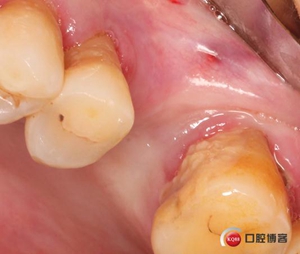

切開翻瓣。

植入一顆4.5x11.5mm長度植體。

半年后修復。